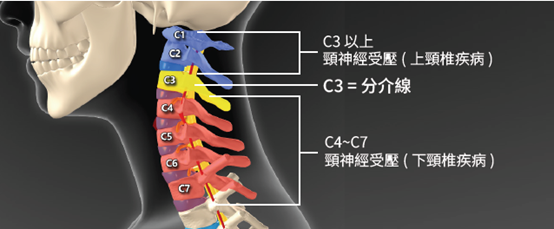

頸椎結構圖:

主要頸源性頭暈、頭痛的成因: (1)上頸椎神經受壓:

因為頸椎分為上頸椎和下頸椎,頸椎C3節為分介線,C3以上椎節為上頸椎節,C3以下椎節為下頸椎節。凡是上頸椎神經受壓,例如:椎間盤突出、椎孔狹窄、椎體移位或下陷,都會有機會導致前額痛、後枕痛、眼窩痛、上頸椎痛。